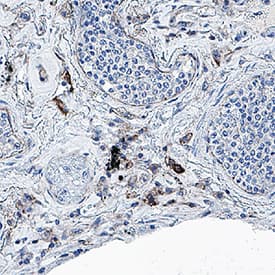

SARS-CoV-2 Envelope in SARS-CoV-2 infected human lung.

SARS-CoV-2 Envelope was detected in immersion fixed paraffin-embedded sections of SARS-CoV-2 infected human lung using Mouse Anti-SARS-CoV-2 Envelope Monoclonal Antibody (Catalog # MAB10925) at 5 µg/mL for 1 hour at room temperature followed by incubation with the Anti-Mouse IgG VisUCyte™ HRP Polymer Antibody (VC001). Before incubation with the primary antibody, tissue was subjected to heat-induced epitope retrieval using Antigen Retrieval Reagent-Basic (CTS013). Tissue was stained using DAB (brown) and counterstained with hematoxylin (blue). Specific staining was localized to immunoreactive profiles scattered throughout the tissue. Staining was performed using our protocol for IHC Staining with VisUCyte HRP Polymer Detection Reagents.